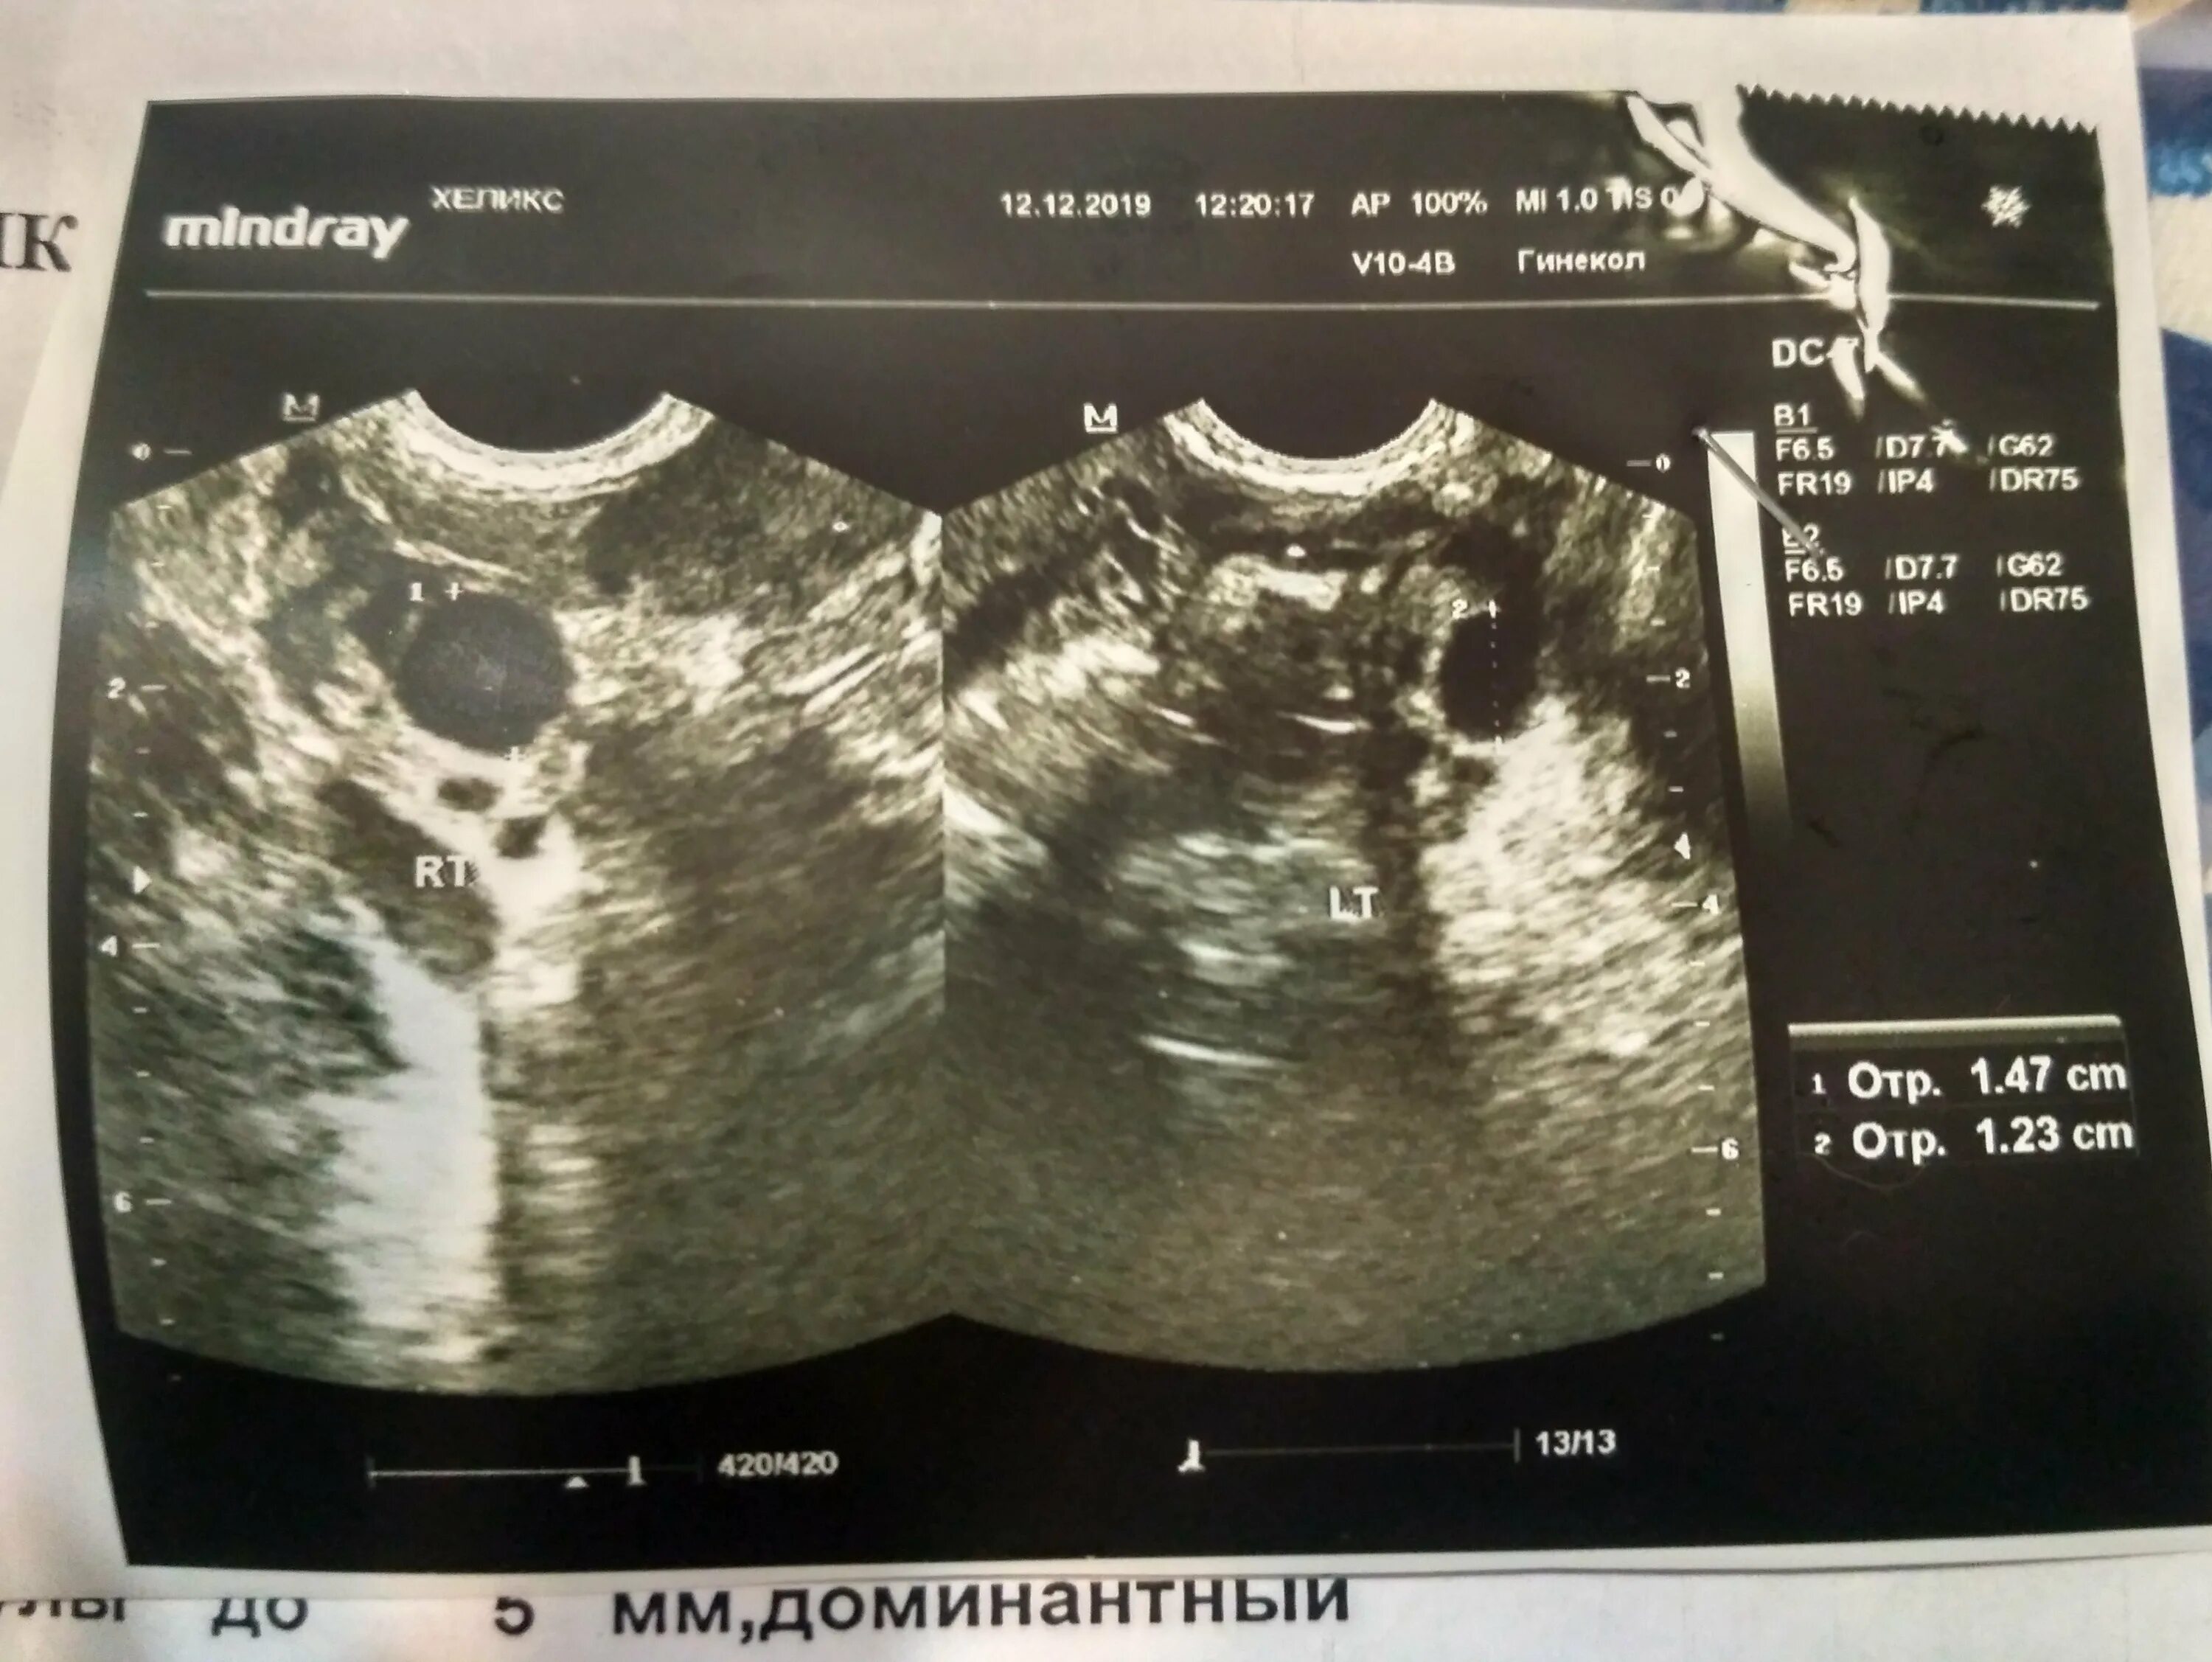

Эндометрия соответствует 2 фазе